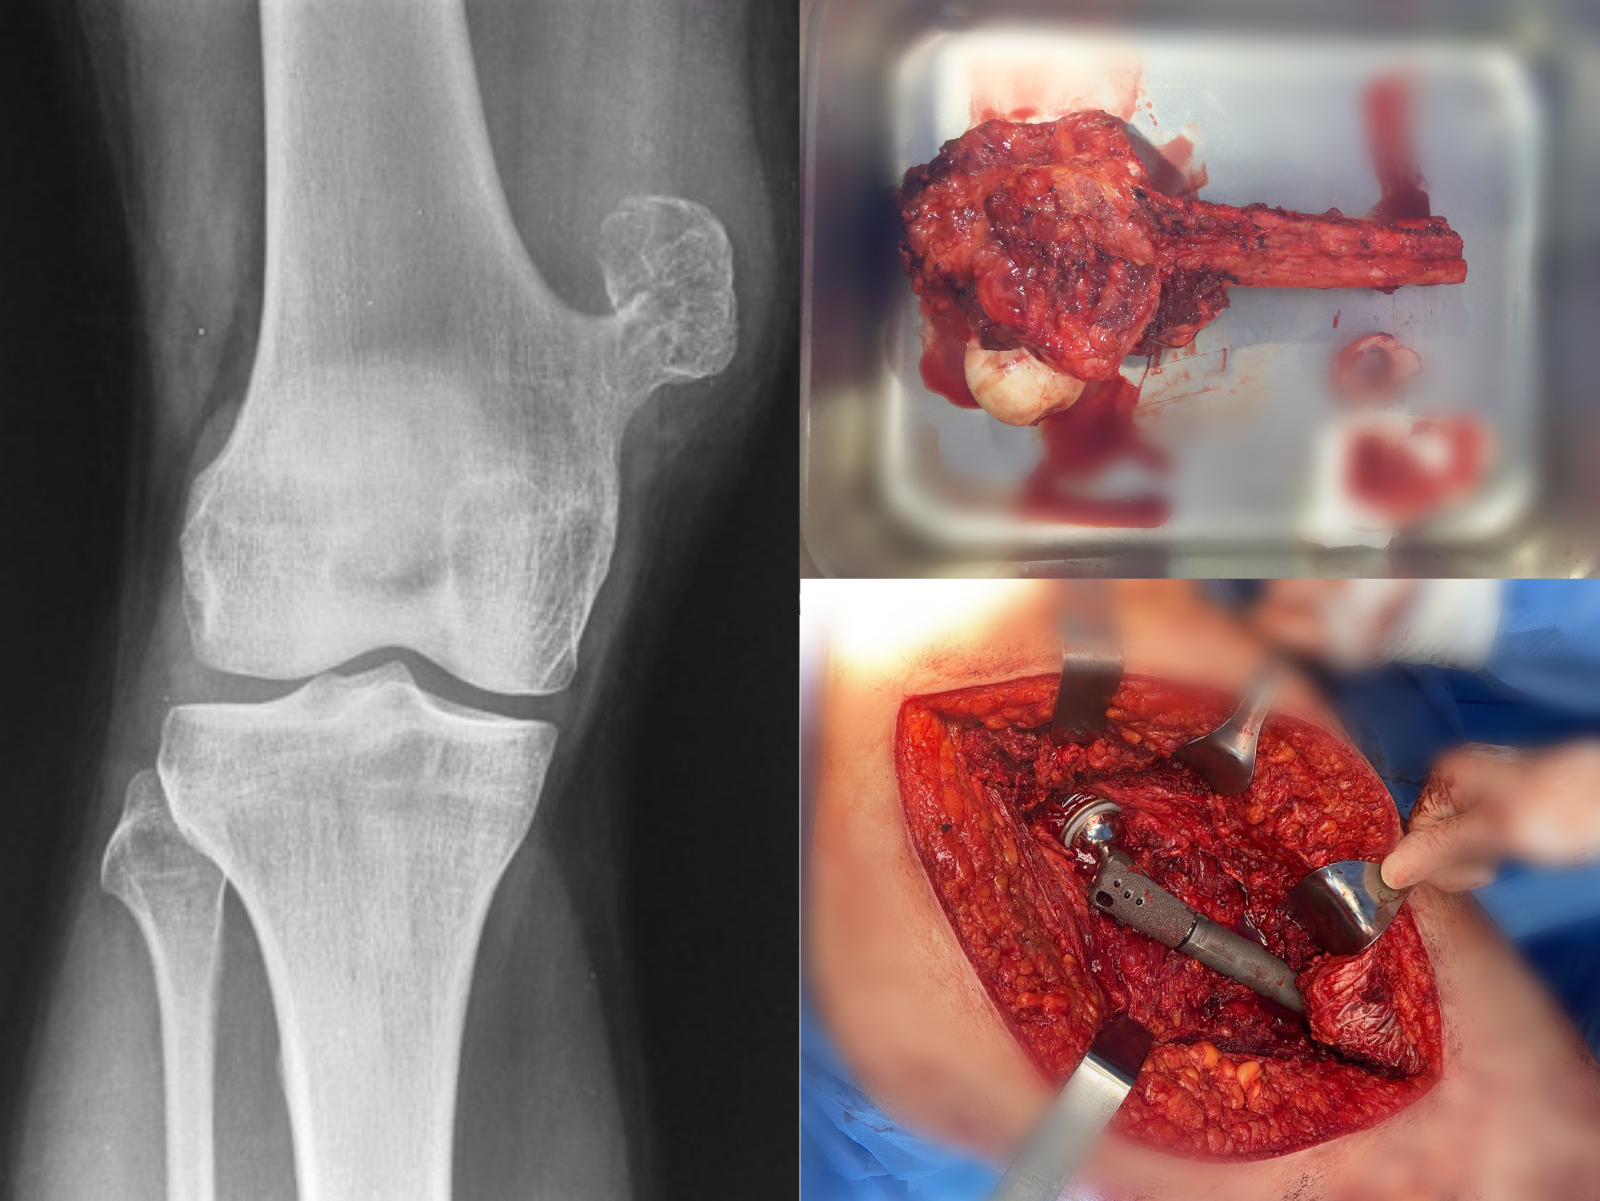

tumores oseos

Osteocondroma

Quiste óseo

Osteosarcoma

Sarcoma de Ewing

Metástasis a hueso

Fracturas patológicas